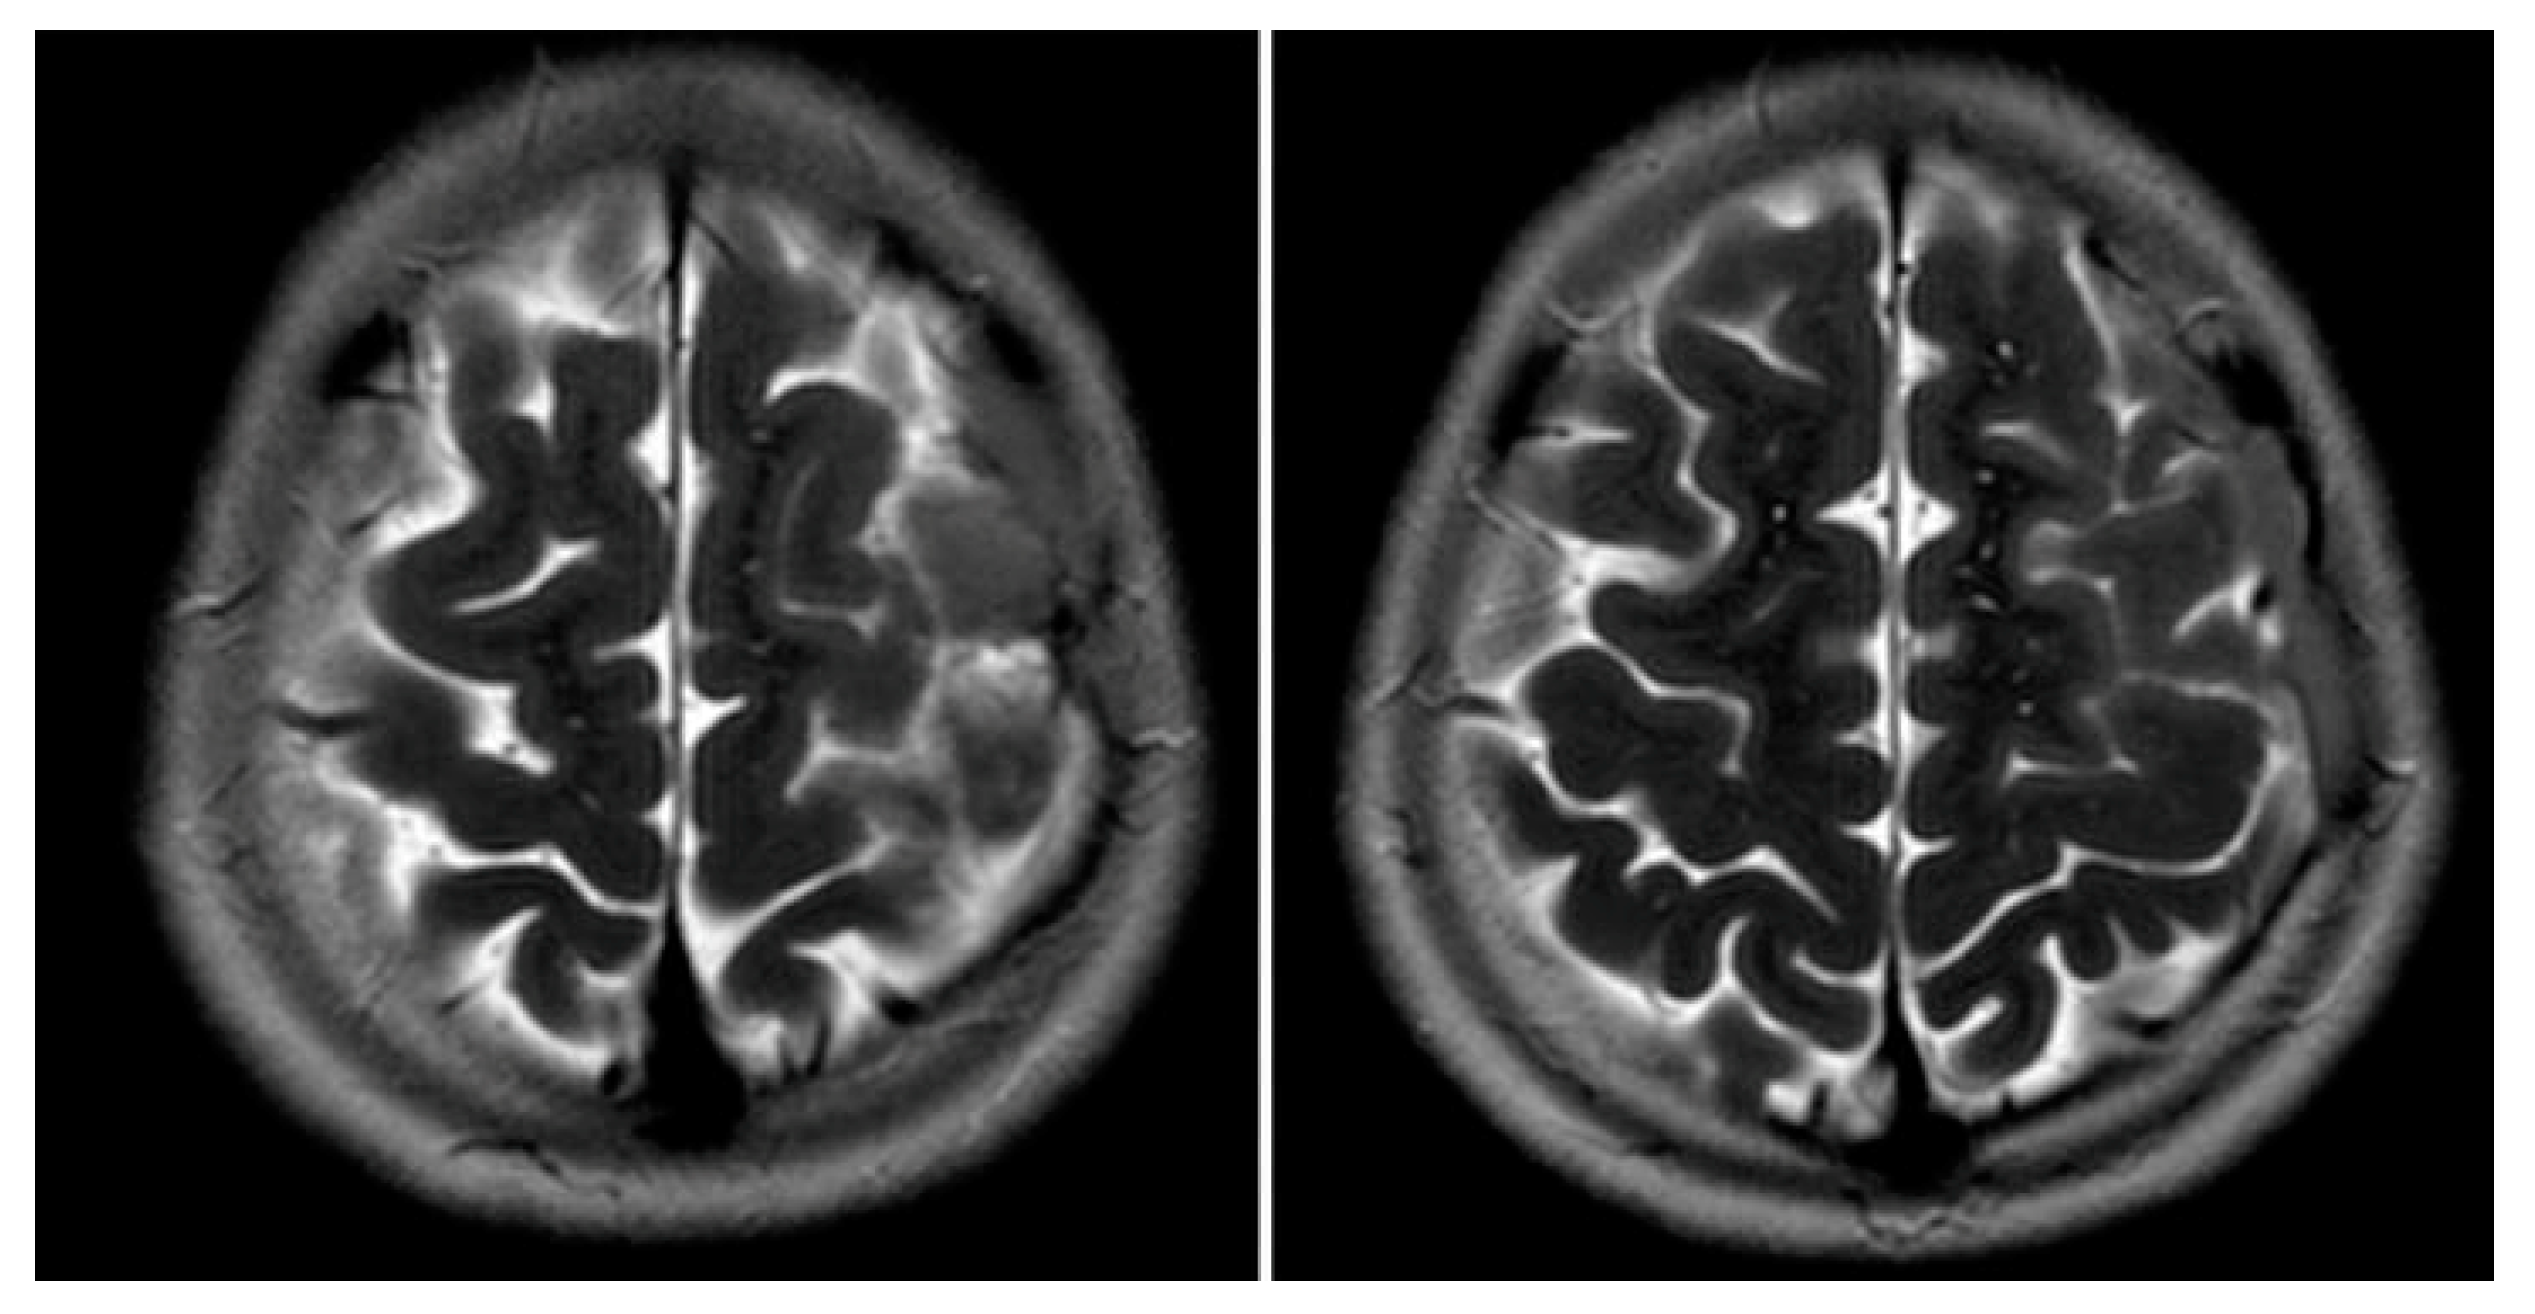

Figure 4. MRI T2WI, axial section in 2012. An extra-axial, well defined CSF structure lesion is identified in the left vertex with the following measurements: anteroposterior, 64 mm; oblique craniocaudal, 53 mm; transverse dimensions, 23 mm. This lesion causes a moderate compression effect of the underlying frontal and parietal gyri at the vertex with scalloping of the inner table. These findings are consistent with a moderate-sized arachnoid cyst at the left frontoparietal vertex.

Figure 1 and Figure 2 reveal a change in signal of arachnoid cyst suggestive of interval hemorrhage with a thin subdural hematoma along its inferior aspect. Minimal edema in the subjacent Rolandic cortex was present. Given the patient’s stroke-like presentation, an MRA of head and neck was administered, which was found to be normal. The findings, with a comparison of the previous MRI of the patient at age 4 (Figure 3 and Figure 4), are consistent with a ruptured arachnoid cyst. No acute neurosurgical intervention was performed due to the absence of raised intracranial pressure and reduction of neurological symptoms. A routine EEG performed in the emergency department exhibited interictal epileptiform discharges over the left and right central–temporal region during drowsy and sleep states, suggestive of increased risk for partial seizures from these regions.